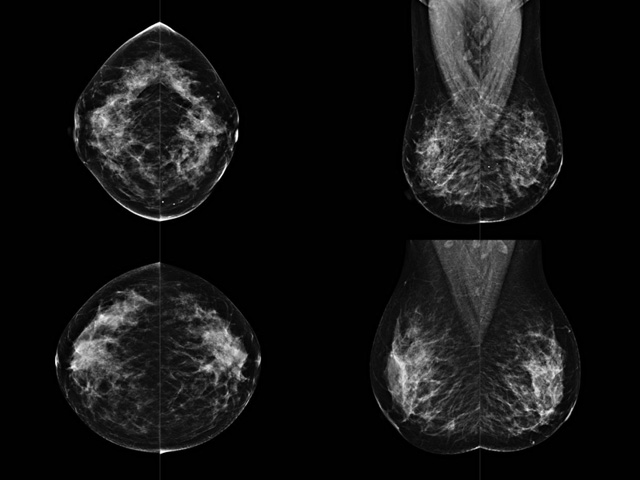

乳房檢查時候要注意一些細節,需要更深入的了解這樣才能使檢查更準確。乳腺DR是乳腺癌的篩查診斷工具設備。是乳房方麵檢查的重要影像方法。它可以臨床檢查出早期的乳腺癌。可以判斷良性惡性。因為它可以檢查出早期的病變。對良性惡性檢查的準確率達到90%以上。發病高峰年齡為45歲到54歲。50歲檢查出來乳腺癌病患,可以讓死亡率下降3成。所以30-40歲女性每年做一次乳腺DR檢查。40歲以上就一年兩次。如果家族史有乳腺癌的30歲以下也需要做檢查。清晰顯示乳腺各層組織嚴重的乳腺增生,乳腺炎,乳腺外傷也建議1年檢查一次。極大提高了早期乳腺癌的敏感度和診斷率。

大角度、高質量的乳腺檢查,可以讓女性帶來身體健康安全。為醫生提供了高清影像數據。乳腺檢查時候各個部位影像顯示出來。白色乳腺導管跟纖維結締組織。模糊的是脂肪。病變一般是不透明的白色。有需要放大來檢查。乳腺DR沒有重疊偽影。輻射劑量更少。因為乳腺癌發病每年都有所提高,對女性都造成了嚴重的身體健康危害。早做檢查早治療是不可忽視的舉措。可以大大的降低死亡率。保證身體健康。一般檢查避開經期,來完7天左右是最佳的檢查時間。絕經的女性就沒有要求。孕婦不參加乳腺DR檢查, 6個月內準備妊娠的婦女也不宜行此檢查。